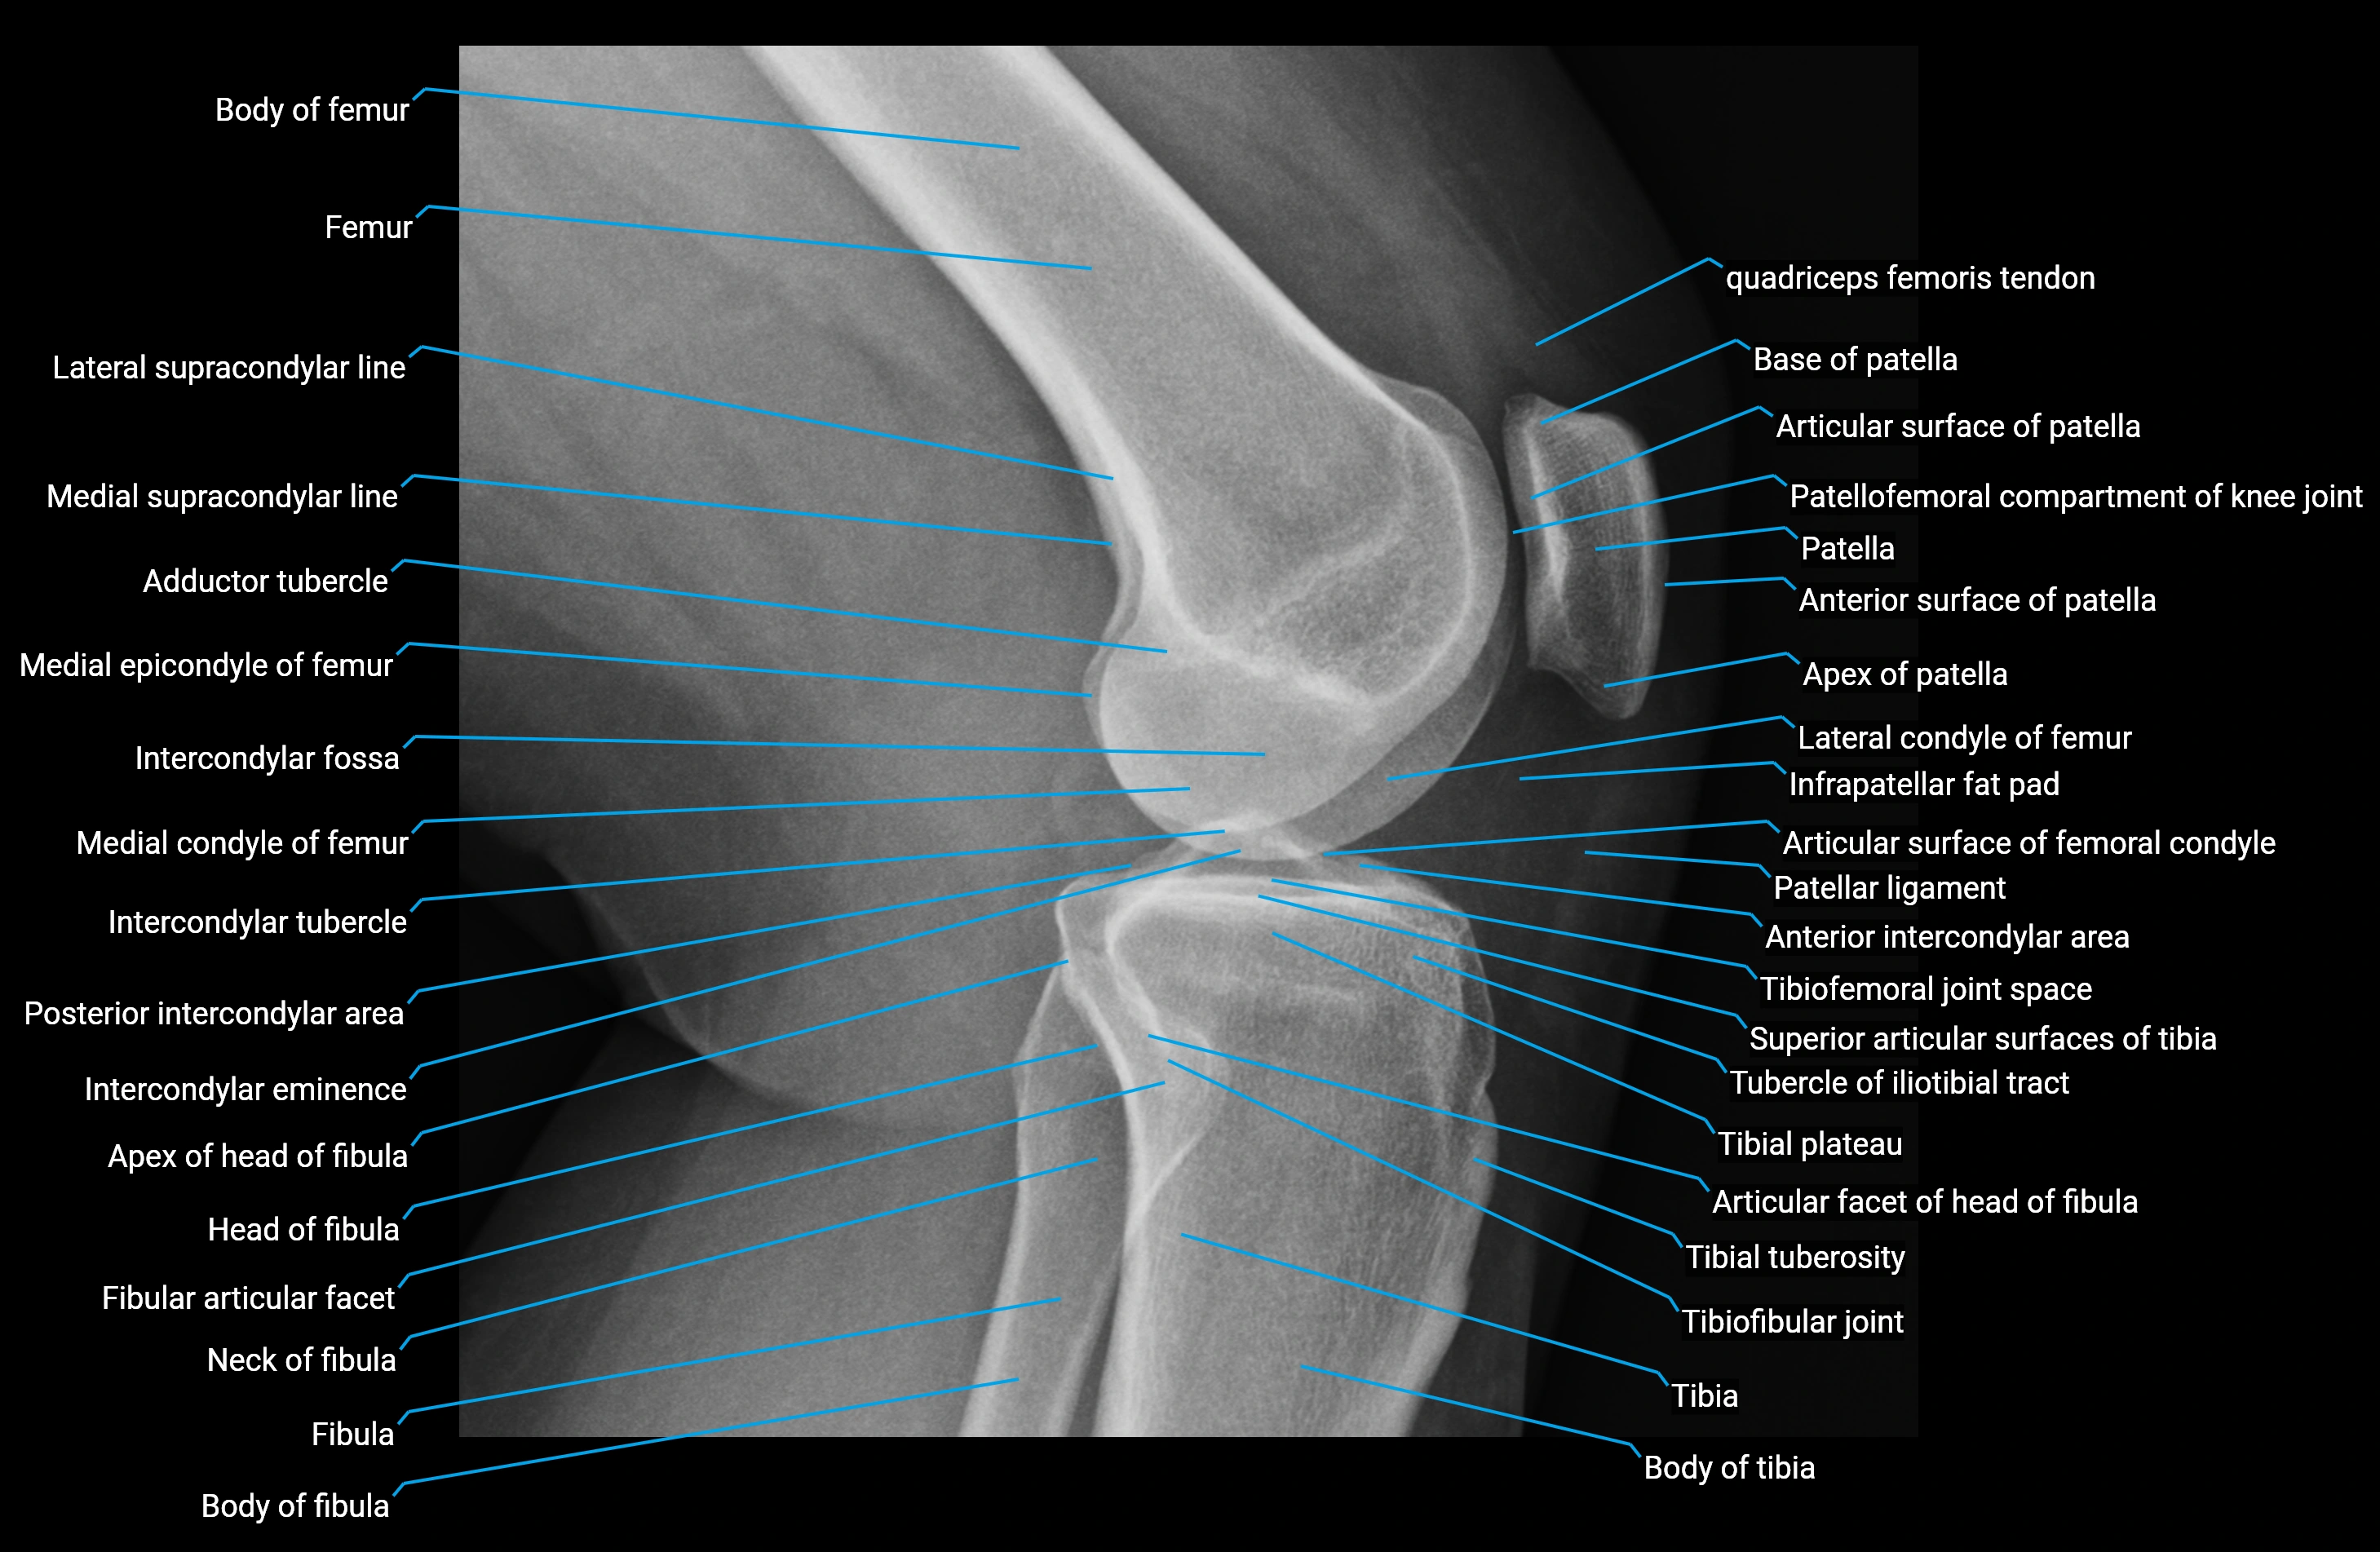

X-ray appearance

Plain radiographs (AP and lateral knee views):

• Adductor tubercle: Small bony prominence on the superior-medial aspect of the distal femur

• Cortical outline: Well-defined and continuous with femoral cortex

• Best visualized: On oblique or lateral projections